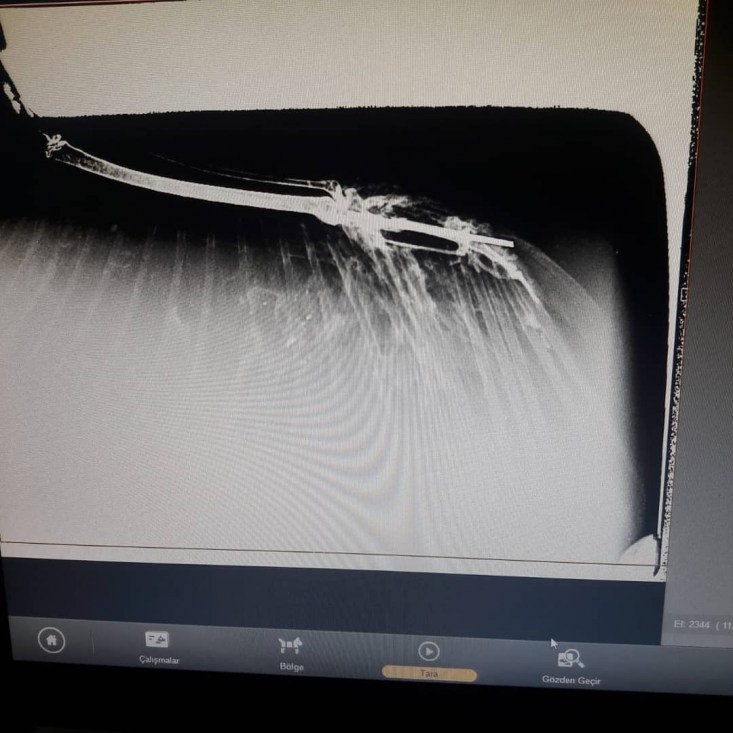

yapılmak üzere ERVET veteriner hekimliğine getirildi. Saçmalardan dolayı

kanatlarında ve kemiklerde kırılmalar meydana gelen Doğan kuşları çekilen

röntgenin ardından tedavilerine başlandı.

tarafından getirildi bu kuşumuz. Önce röntgenini çektik. Röntgeninde kemiğinin

saçma ile parçalandığını, darmadağınına yakın bir parçalanma yaşamış kemiği.

Pazar günü bunu operasyona aldık. Kırık kemiğinin parçalarını düzelttik. Kalan

kemiklerin arasındaki bağlantıyı sağladık. Önce tabi şoka giriyorlar bu durum